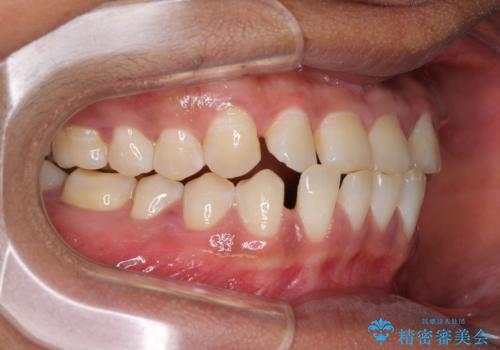

反対咬合の改善 途中で出産をしながらワイヤー矯正

- 前歯の隙間と反対咬合を気にして来院された患者様です。

マウスピース矯正も提案しましたが、しっかりと使用する自信がないとのことで、ワイヤー装置により矯正治療を行うこととしました。

咬合力が強く、反対咬合の改善に時間がかかりましたが、その後はスムーズに進めることができました。

途中、妊娠と出産があり、治療が中断したため、治療期間は延びましたが、出産も矯正治療も無事に終えることができました。